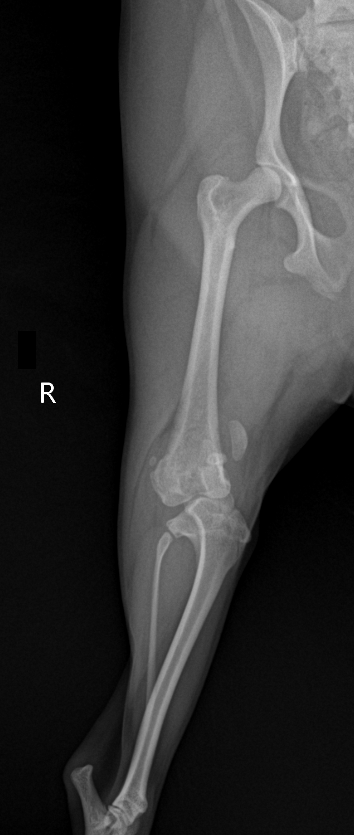

X-ray

슬개골 탈구, 대퇴골 만곡과 경골 심한 회내 동반